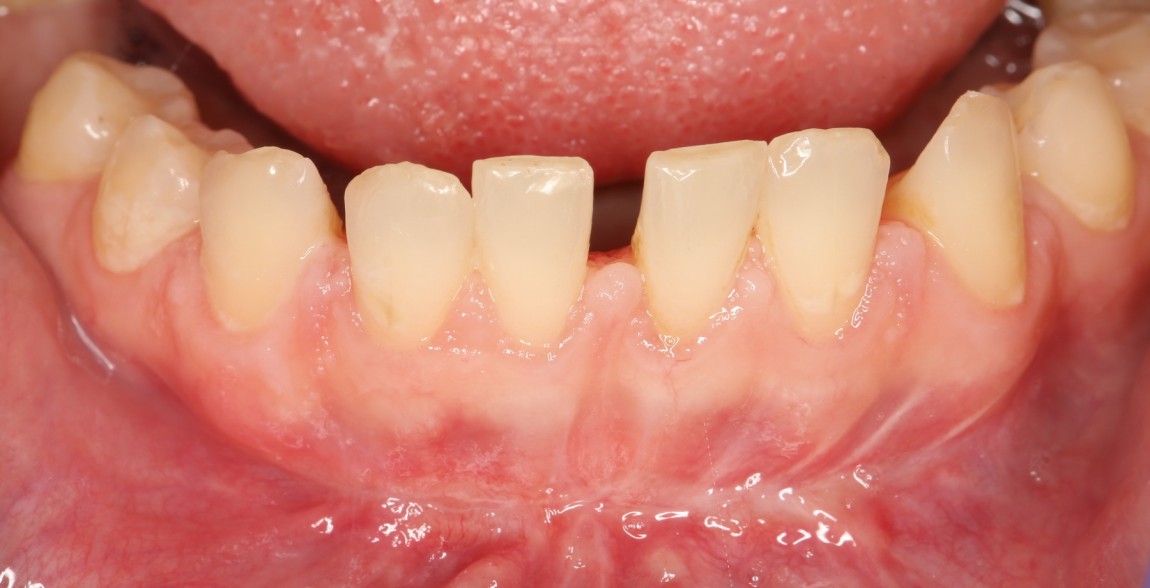

Пациентка, чуть больше 25 лет, готовится к ортодонтическому лечению. Одна из проблем, которую необходимо решить до начала ортодонтии — мелкое преддверие полости рта. Для этого необходима вестибулопластика (углубление преддверия).

В норме расстояние от нижней границы межзубного сосочка до переходной складки (места перехода прикрепленной десны в подвижную слизистую) составляет 5-7 мм, это и считается глубиной преддверия. В данном случае мы имеем менее 4 мм:

Подобная клиническая ситуация чревата, в первую очередь, риском возникновения рецессий десны и развития пародонтита, который нередко приводит к потере зубов.

Сравните с тем, что было:

Со временем, рубцы размягчатся и станут почти незаметными. Теперь пациентка может спокойно приступать к исправлению прикуса, которое, в свою очередь, является частью еще более грандиозного плана стоматологического лечения: предстоит еще и имплантация, и протезирование, и много чего еще.